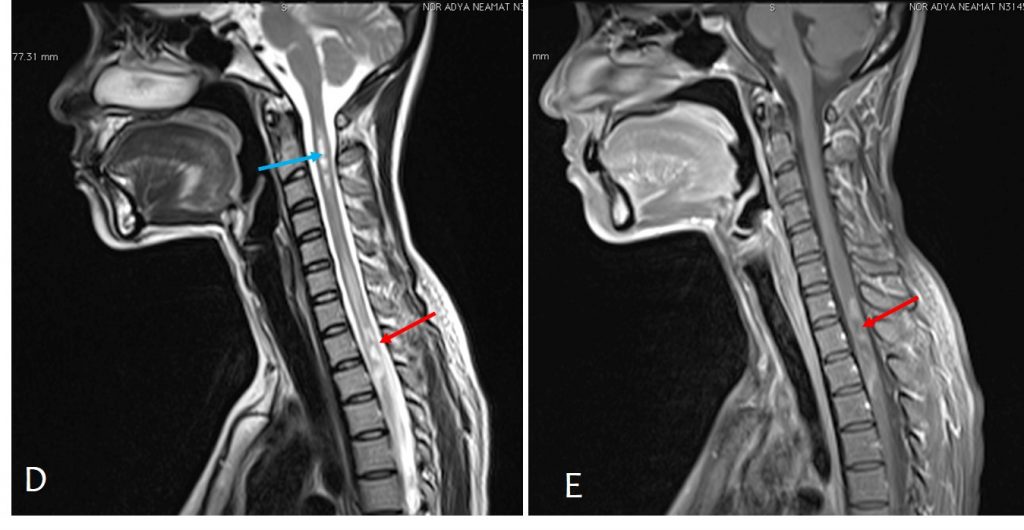

Neuromyelitis optica Radiology Cases Ring Enhancement Radiopaedia the enhancement of multiple sclerosis plaques may be faint, with a thin and often incomplete rim (“open ring. refaey m, thibodeau r, catchpoole s, et al. Notice that the open ring points towards the ventricle (arrow), which. the open ring sign is a relatively specific sign for demyelination, most commonly multiple sclerosis (ms), and is helpful in. Ring Enhancement Radiopaedia.